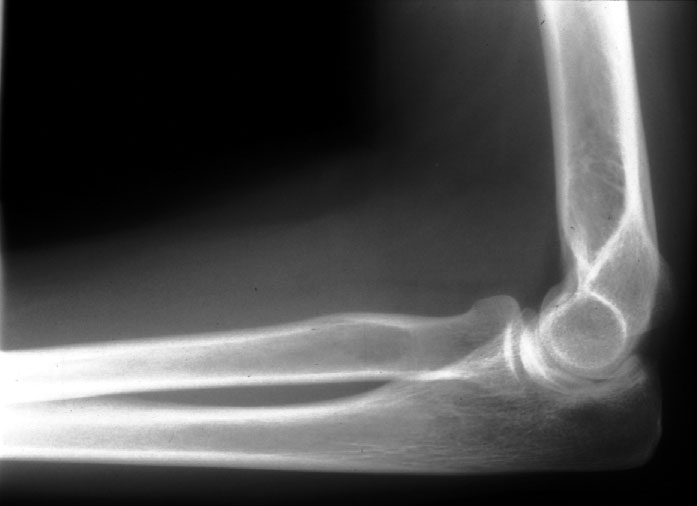

Normal Elbow (lateral) -- Identify: humerus, readius, ulna, capitulum,

radial head, olecranon